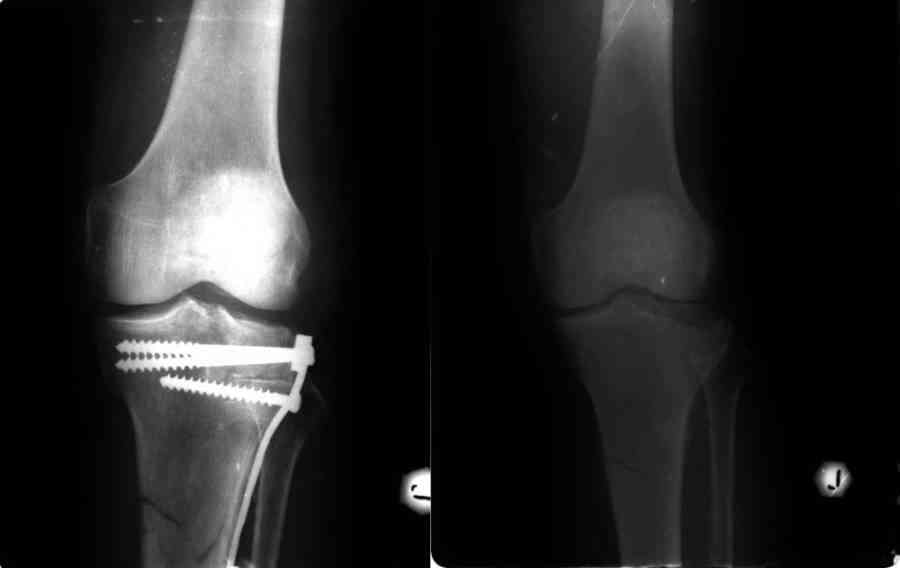

Пациенту 67 лет, в июле 2007 года выполнена операция по поводу импрессионного перелома латерального мыщелка и закрытого перелома вехней трети левой б/берцовой кости, перелома латерального межмыщелкового возвышения.

К тому же выявлен перелом нижнего полюса левого надколенника без смещения (остеосинтез не проводился). Кататравма, спрыгнул с высоты 2 метров на прямые ноги.

Выполнен остеосинтез опорной платиной с подъемом плато и замещением дефекта аутокостью из крыла тазовой кости. Артротомия и ревизия коленного сустава не проводились. П/операционный период гладкий.

Не исключена несостоятельность разгибательного аппарата коленного сустава (перелом надколенника, поврежедение ССН, удерживающего аппарата надколенника и т.п.) Жаль что нет рентгенограмм в динамике.